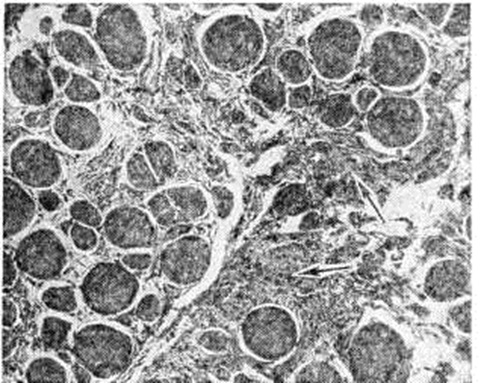

При гранулематозном миозите, представляющем собой мышечную форму саркоидоза, находят узелковые или диффузные инфильтраты из эпителиопдных клеток, гистиоцитов, лимфоцитов и единичных гигантских клеток типа Пирогова — Лангханса (смотри полный свод знаний Гигантские клетки). При токсических Миозит преобладают некротические изменения мышечных волокон (миолиз, коагуляционный некроз) с сохранением сарколеммы и скудной воспалительной реакцией в эндои перимизии. При профессиональных Миозит, обусловленных длительным физических напряжением, определяются очаговые дистрофические и атрофические изменения мышечных волокон, склероз эндо и перимизия. Гетеротопическая оссификация, являющаяся патологический формой костеобразования (смотри полный свод знаний Кость), может развиваться во многих тканях и органах, в том числе и в мышцах. Наиболее важной формой гетеротопической оссификации является оссифицирующий Миозит При травматическом оссифицирующем Миозит в центре очагов уплотнения определяется молодая соединительная ткань с активно пролиферирующими фибробластами, на периферии — кальцифицированное основное вещество, незрелые и зрелые костные перекладины. Оссифицирующий Миозит нетравматического генеза представляет собой универсальный кальциноз мышц (смотри полный свод знаний Кальциноз), в основе которого лежит фибродисплазия. Гистологически в узлах уплотнения на ранних стадиях патологический процесса находят активно пролиферирующие фибробластоподобные клетки. Их цитоплазма содержит большое количество гликопротеида, богатого маннозой. Электронно-микроскопически клетки напоминают опухолевые (гиперхромные ядра, гиперплазированные цитоплазматический ретикулум и пластинчатый комплекс). В межуточной ткани отмечается накопление гликозаминогликанов (гиалуроновая и хондроитинсерная кислоты). Сформированный узел имеет зональное строение: в центре — фиброзная ткань из фибробластоподобных клеток, по периферии — участки остеоида. В дальнейшем в новообразованные костные перекладины откладывается известь. Кроме метаплазии соединительной ткани в костную, отмечается метаплазия её в хрящ с последующим энхондральным окостенением. Костные участки принимают ветвистую форму с губчатым строением во внутренних отделах и компактным в наружных. В старых костных образованиях появляется костный мозг.